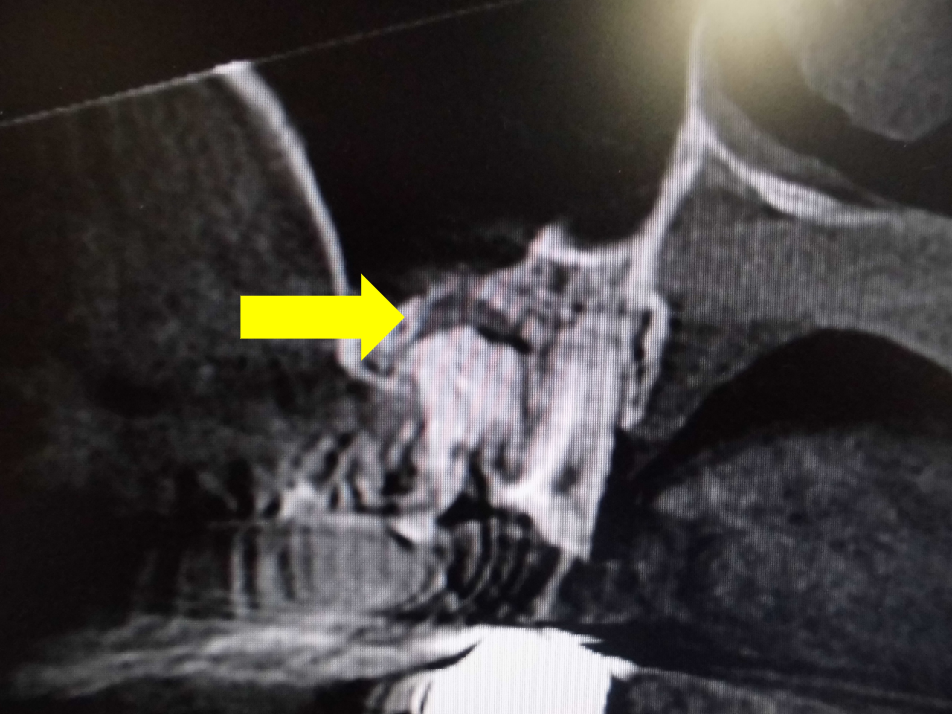

レントゲンでは不明な根尖病巣がCTでははっきり写ります。

同じ患者様です。根管が樋状根になっているのもわかります。